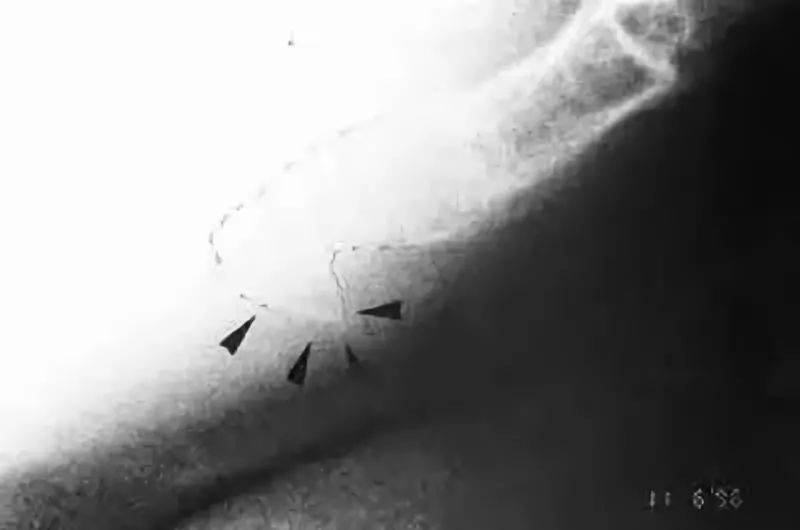

3骨刺(Coccygeal spicule)

在尾骨尖端的背侧面,有时可以看到尖尖的赘生物即是,我们轻触皮下的部份就就可以感觉到。患者坐着时,有可能会因为压到而感到不舒服。这个骨刺的现象最常在"固定"的尾骨上发现。